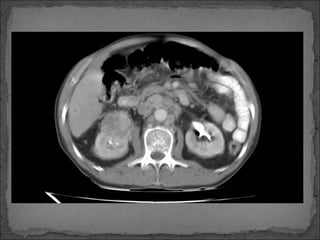

Obstrucción de las arterias principales abdominales:

 Celíacas

 Mesentérica superior

 Renales

 Mesentérica inferior

TC Contrastada

27 por ciento

Obstrucción de lasarterias principales abdominales:  Celíacas  Mesentérica superior  Renales  Mesentérica inferior TC Contrastada 27 por ciento